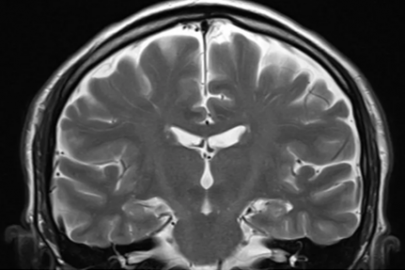

Timp aproximativ de lectură: 6 minute Aceasta este tema Zilei mondiale de luptă împotriva accidentului vascular cerebral 2025 și îndemnul campaniei Organizației Mondiale a Accidentului Vascular Cerebral (WSO). De ce această temă în acest an? Multe victime ale accidentelor vasculare cerebrale nu primesc tratament la timp deoarece semnele nu sunt observate sau ... Citiți mai mult...